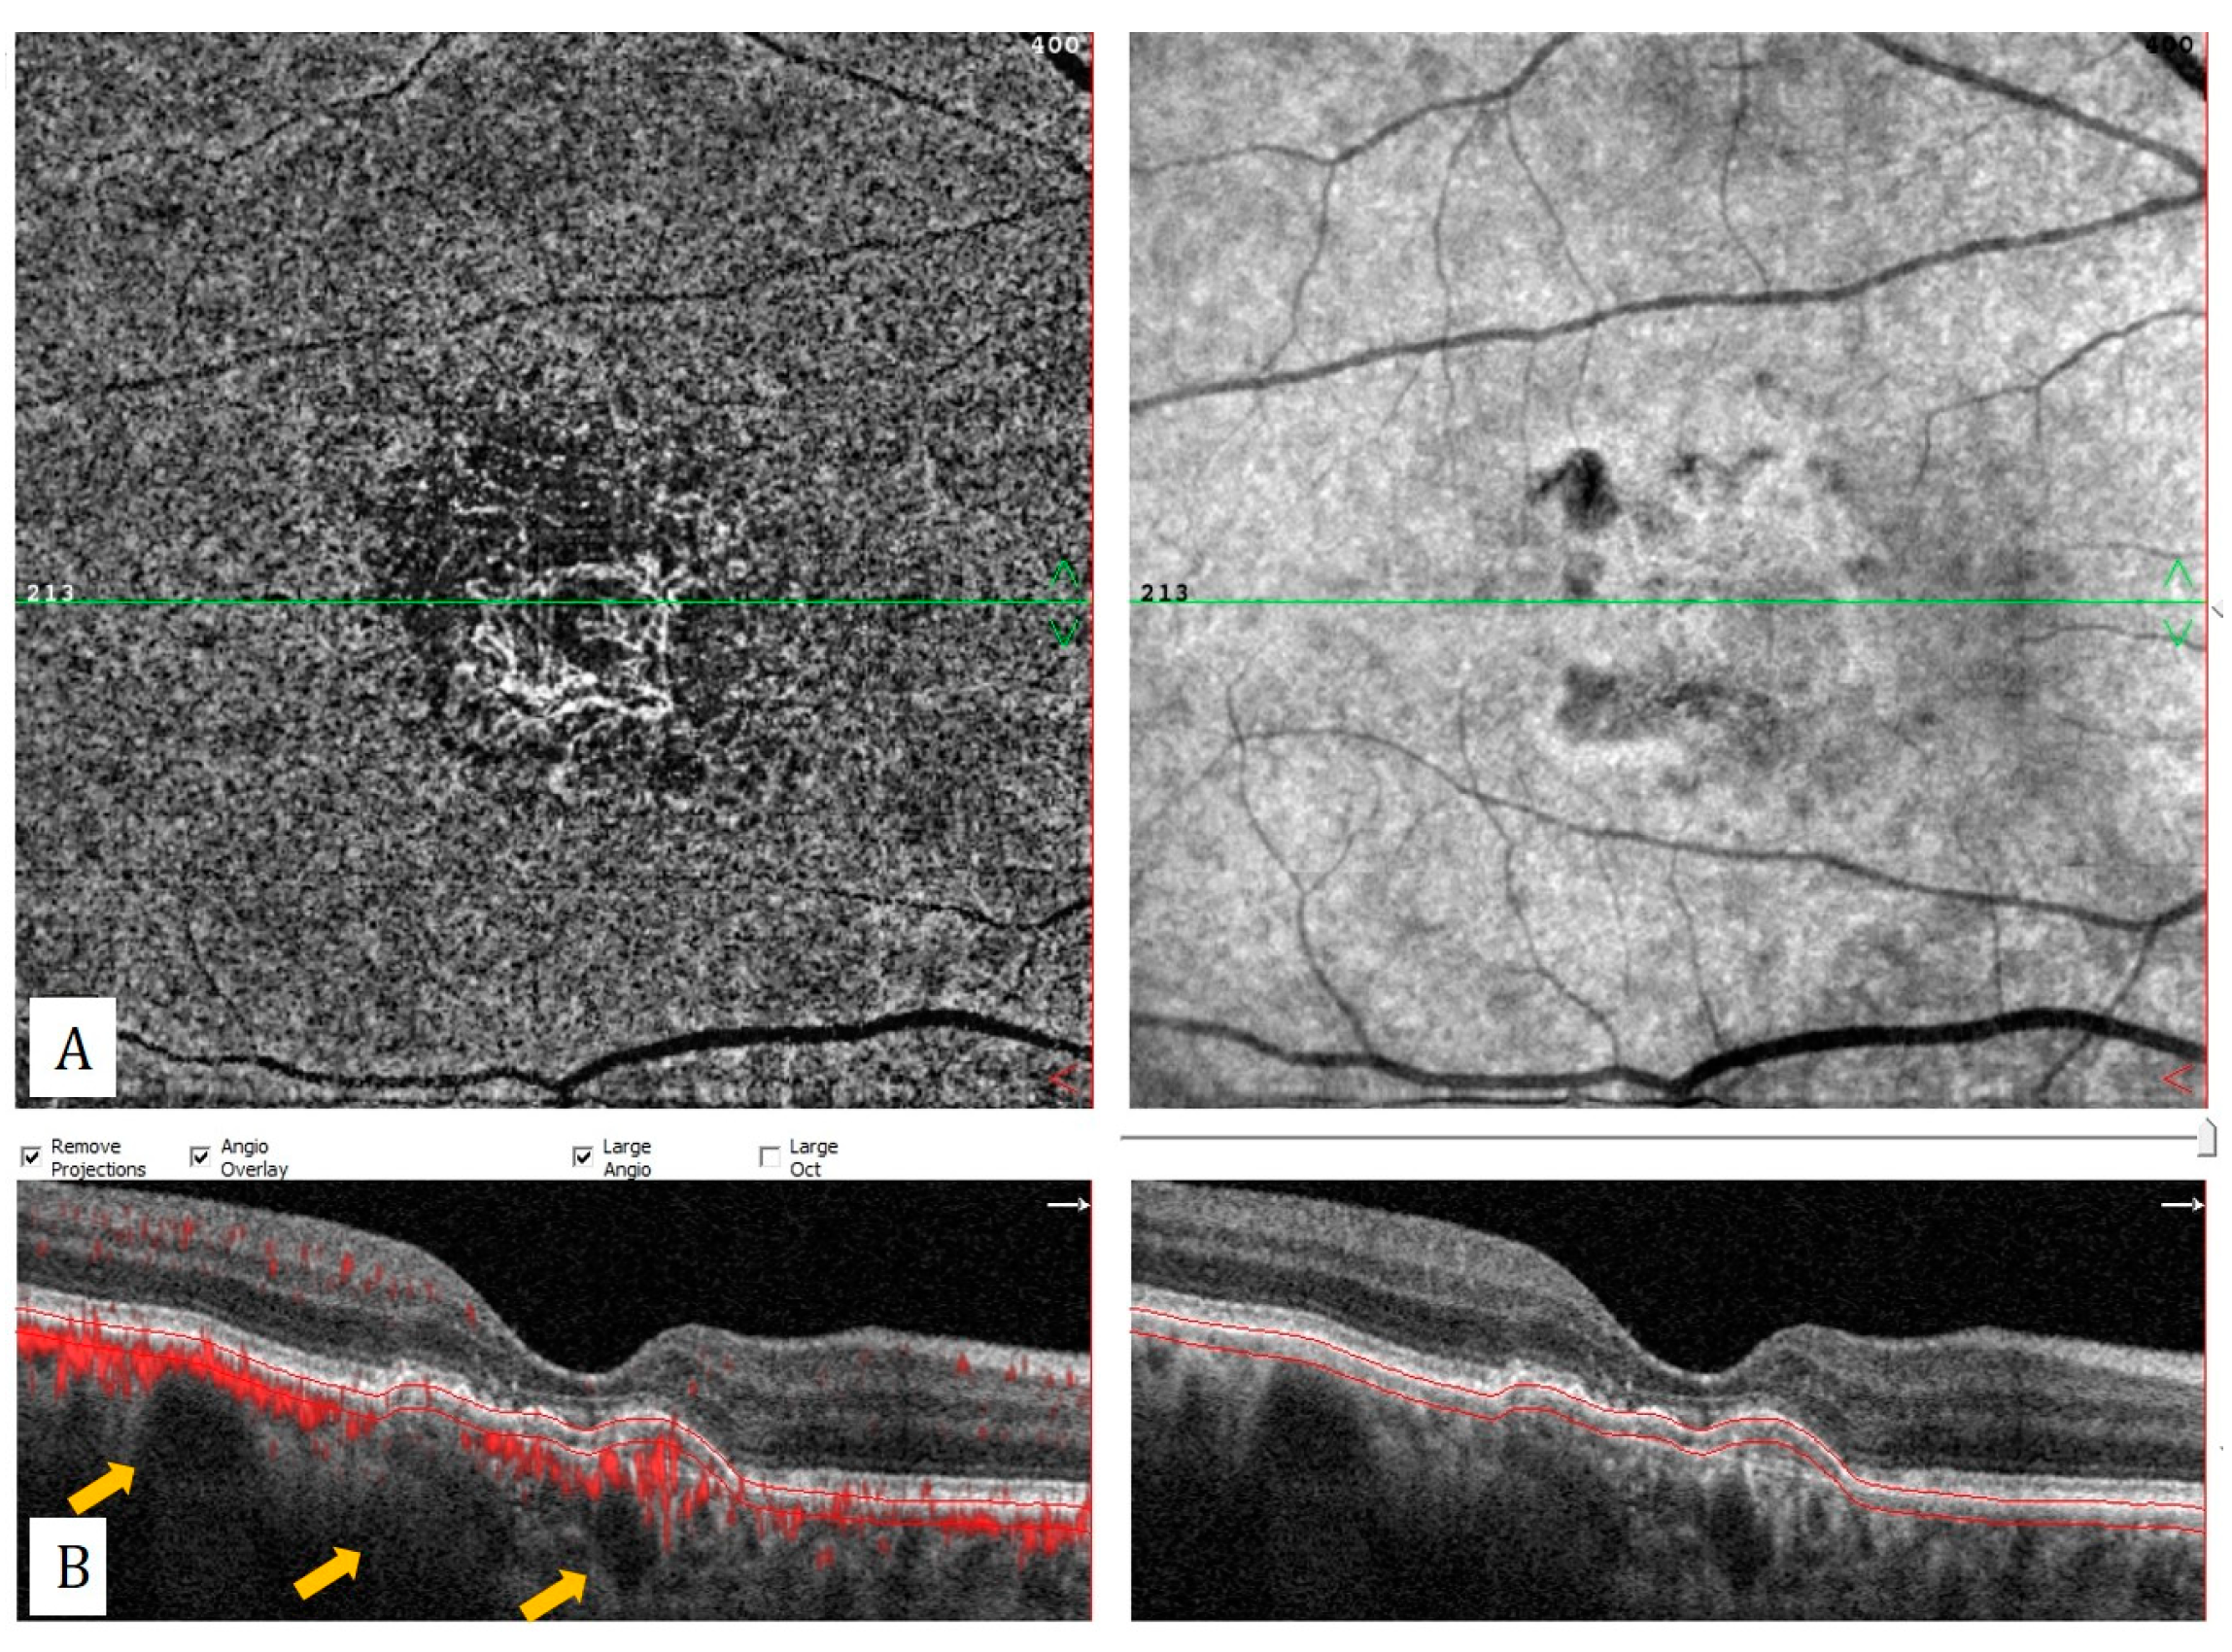

Figure 5. Pachychoroid neovasculopathy: (A) Choriocapillaris slab of optical coherence tomography angiography shows macular neovascularization. (B) Flow-data-superimposed horizontal B-scan reveals flat irregular pigment epithelial detachment with intrinsic flow signal and dilated Haller vessels (yellow arrows).

OCTA is not affected by choroidal hyperpermeability and can show the exact size of the neovascular membranes in PNV cases (Figure 5). However, in 11.8% of ICGA-proven PNV cases, it was stated that OCTA could not identify MNV due to blockage of fluid or hemorrhage [30]. In contrast, chroroidal hyperpermability and the extend of RPE alterations may limit the use of ICGA for the MNV detection in these cases. Demirel et al. reported a higher sensitivity with OCTA in detection of type 1 MNV, compared to conventional dye angiography in cases with pachychoroid spectrum disease [31].